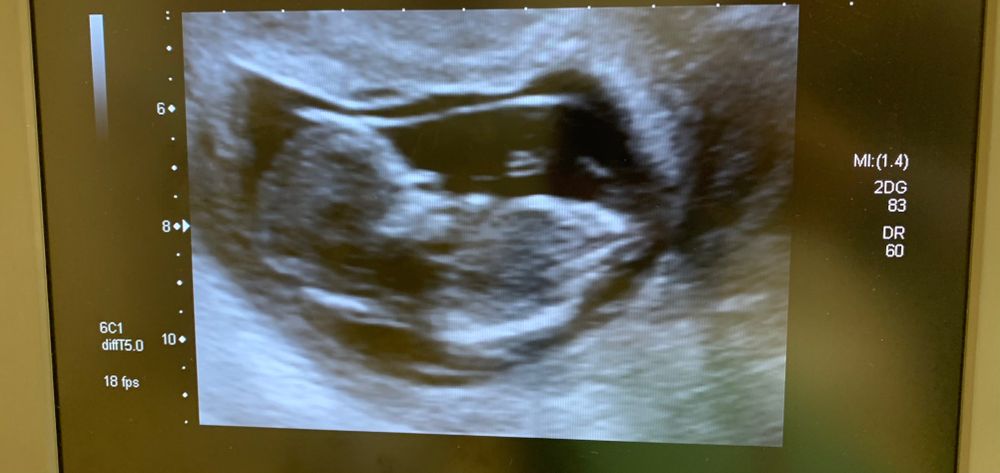

Первое узи - не сказали пол

Всем привет, девочки ! 23 декабря были на первом скрининге , узистка была немногословна, сразу сказала , что пол не определяют 🥺. Знаю , что тут есть эксперты ) Предположите , кого же мы ждём ( очень хочу девочку , муж , естественно, мальчика ).